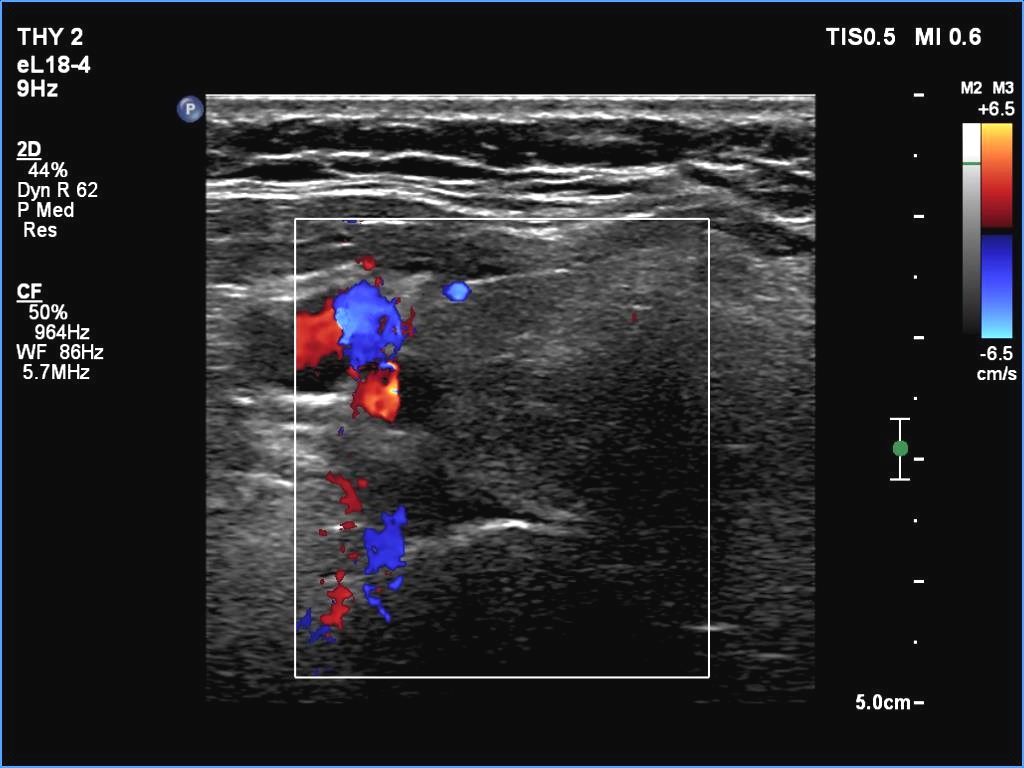

Right lobe, transverse scan, color Doppler mode. The vascularity is scanty.